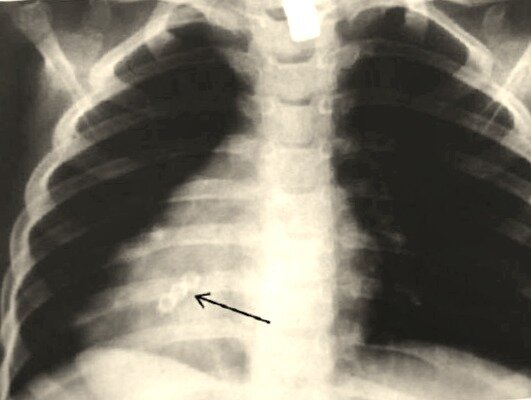

Установить факт наличия постороннего предмета в организме можно только с помощью рентгена, УЗИ или МРТ. Но даже опытные специалисты не поверили своим глазам, когда обнаружили в легких одного мужчины нечто похожее на еловый росток длиной 5 см. Операция по его извлечению подтвердила увиденное. Это оказалась хорошая новость, ведь у кашляющего кровью пациента подозревали страшное заболевание. Предполагают, что он вдохнул семя с воздухом.